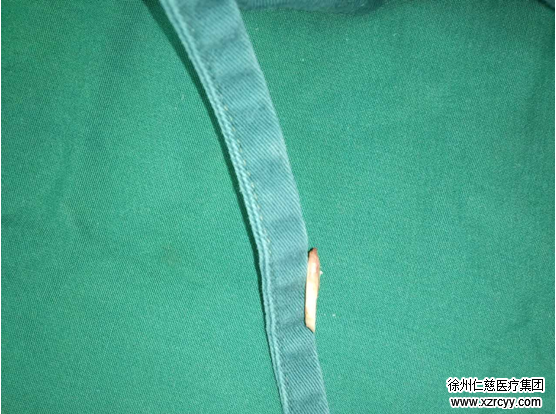

“这个病人已经属于比较严重的了,关节镜下见TFCC浅层已磨损殆尽,深层也破裂不堪,无法修复浅层,只能深层修复,尺骨缩短来解决磨损。”为方便理解,说完,齐主任接着补充“如果将手部结构比喻成一台精密机器,那么尺骨和腕骨则是机器的轴承,TFCC盘则是两个轴承间的缓冲垫。一旦这个缓冲垫坏了,两个轴承(尺骨和腕骨)便会直接摩擦。常年磨损,轴承磨坏了,自然会产生疼痛。”

结合关节镜探查情况,简单交流后,两位专家决定为孙先生做手术,通过截掉约3.5mm尺骨,扩大两个“轴承”间距离,消除疼痛。